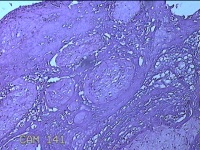

胎盘组织

性别

女

年龄

30岁

临床诊断

妊娠合并中度贫血

一般病史

停经39+2周,B超检查发现羊水偏少6小时。

标本名称

大体所见

灰白暗红色胎盘组织16.5x14.5x3.5㎝一个,表面光滑,血管突出,颜色发暗,绒毛面结节状,有轻度糜烂,暗红色,有少许凝血块,切面见绒毛内有暗红色血液渗出,边缘蜕膜可见多个小血肿,脐带39x1.8x0.3㎝,螺旋状扭曲,切断脐带,见脐血管内有凝血块。